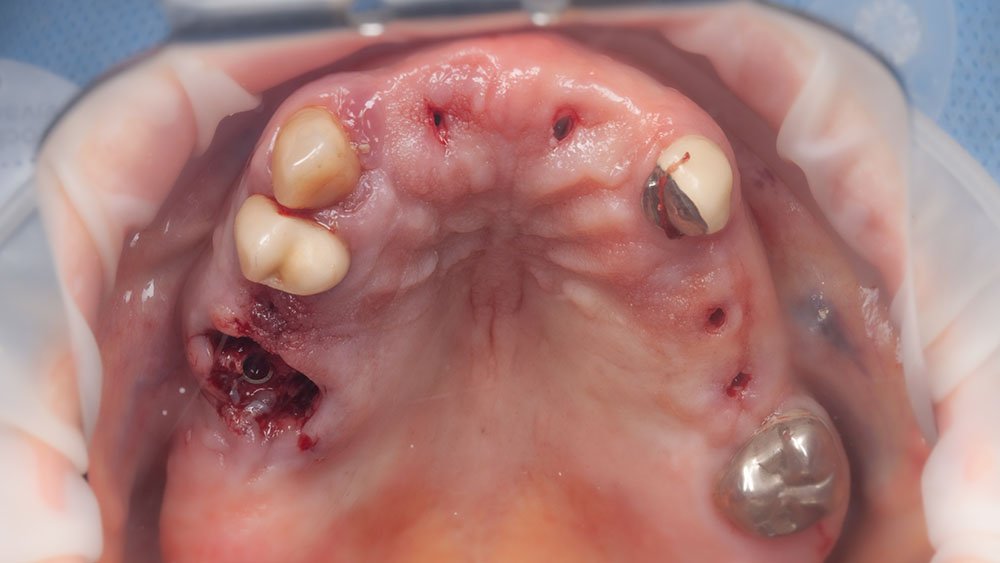

Momento logo após a confecção dos implantes guiados superiores.

Próteses provisórias. Na arcada superior, o tecido gengival será condicionado e na inferior, uma prótese dento-gengival será utilizada.